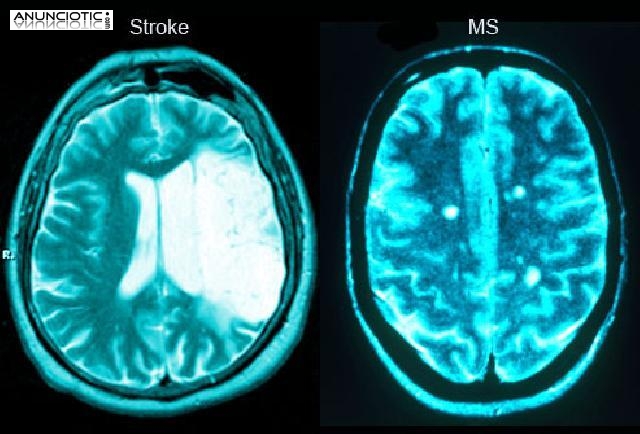

Tratamiento para pacientes con daño cerebral adquirido (Alzheimer, lesionados medulares, ictus, accidentes cerebrovasculares, afasia, ataxia hemiplejias,  ACV, traumatismo craneoencefálico, tumores cerebrales, anoxias cerebrales, Accidentes de Trafico, Problemas en el Lenguaje.

Tratamiento para pacientes con esclerosis múltiple, esclerosis lateral amiotrofica, enfermedad de Parkinson, ataxias y lesiones medulares. Tratamiento para pacientes neuromusculares (Duchenne, Charcot Marie Tooth, Steinert, Becker, miopatías, atrofia muscular espinal...).